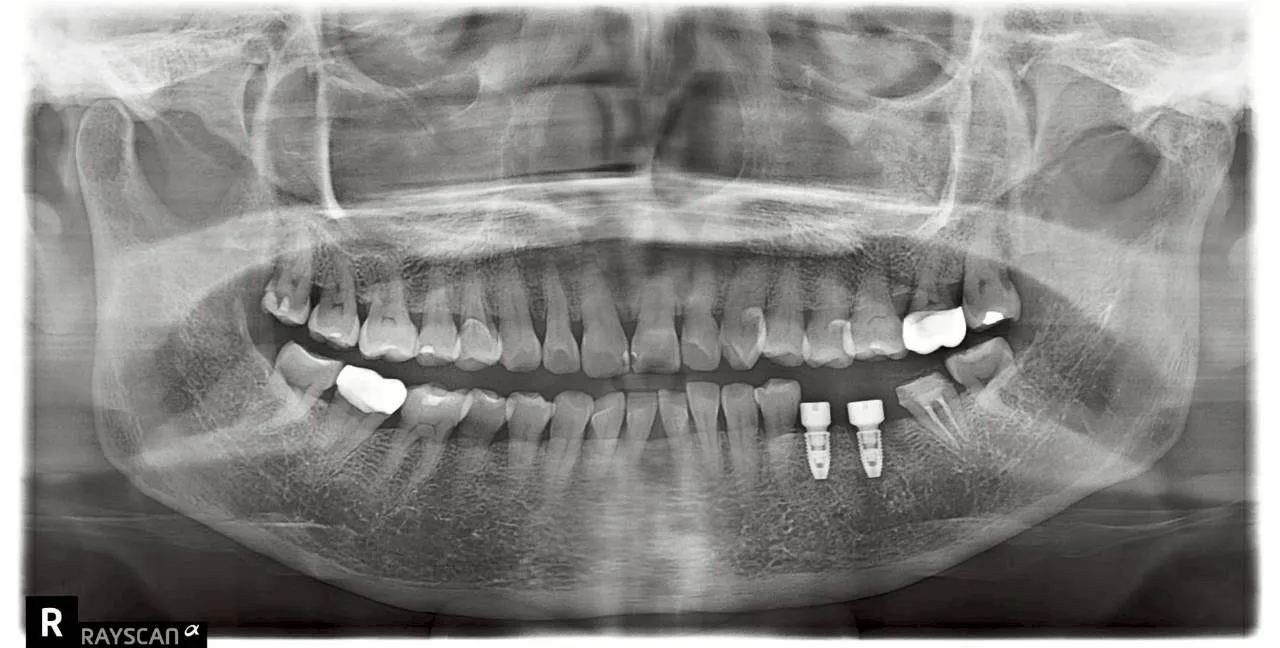

• 植體植入(圖二): 選擇合適直徑與長度的植體,為缺牙區重新打下穩固地基。

• 功能恢復(圖三): 裝上高度精準的假牙冠,完美銜接原有咬合曲線,恢復強勁咬合力。